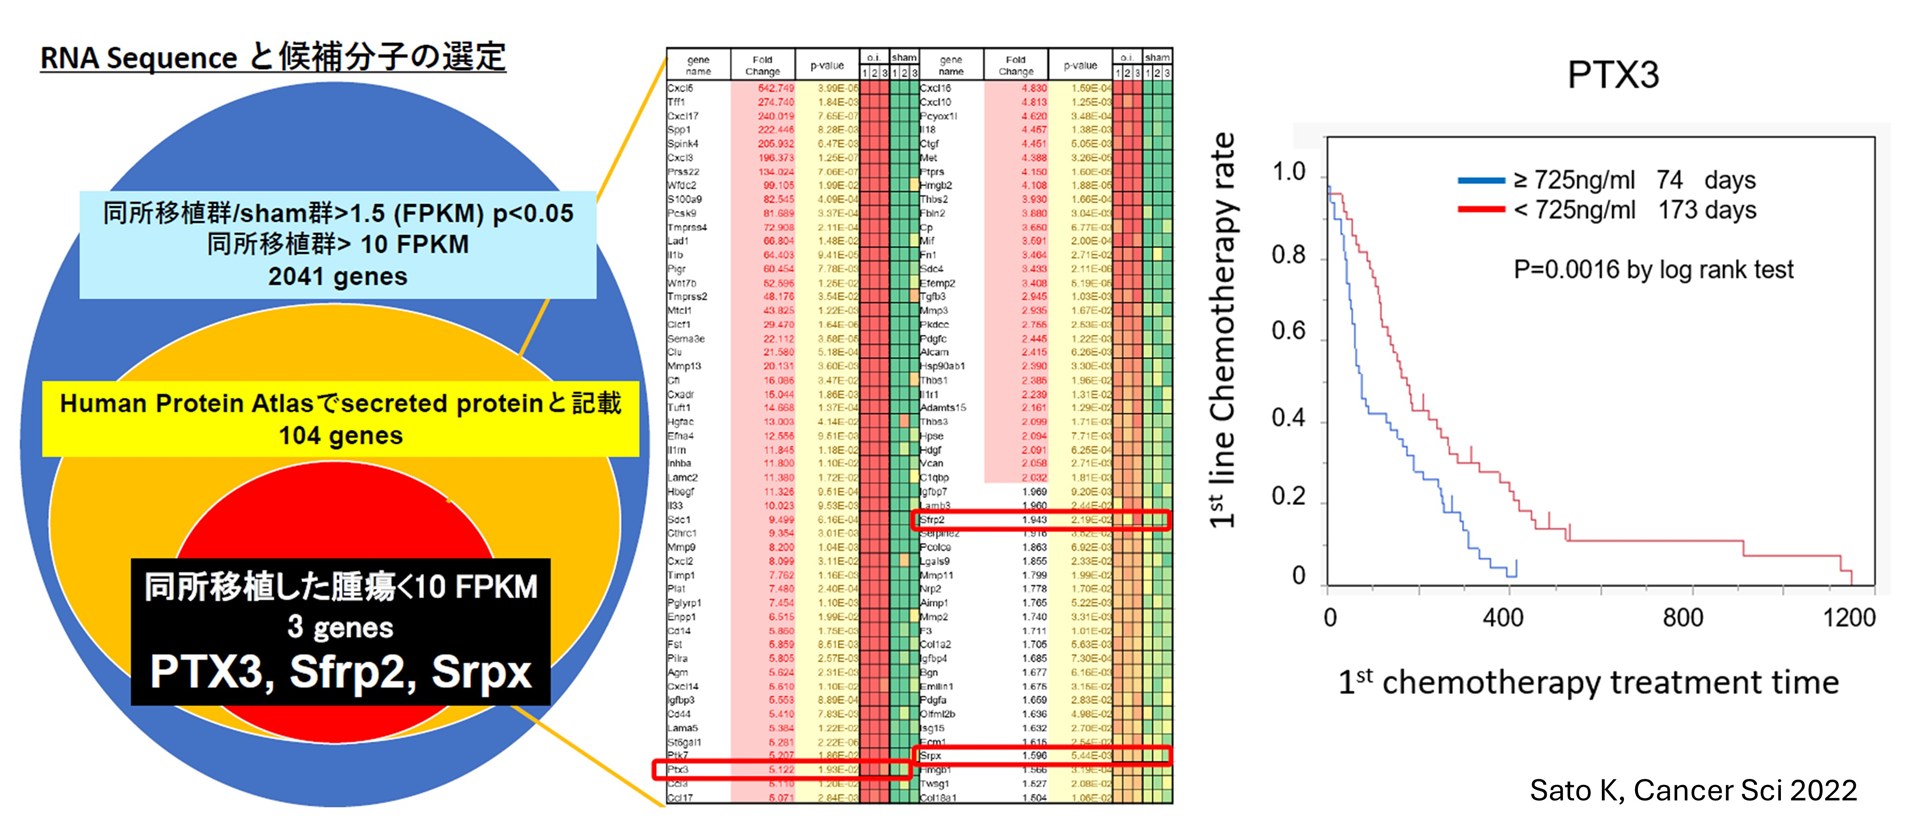

内視鏡診療と連動したトランスレーショナル・基礎研究

内視鏡や診療で得られた臨床検体を活用し、胆膵癌の病態解明につながる基礎・トランスレーショナル研究を展開しています。 これまでに、代謝異常関連炎症と膵癌予後の関連を示した血清Tenascin-C研究8)、膵癌悪液質に関連する血清Pentraxin3の同定9)(下図)など、血清バイオマーカー研究を報告しています。また、腫瘍免疫逃避に関与するRegnase-1の役割10)をはじめ、胆膵疾患の発症・進展機構に迫る基礎研究成果も発信しています11-15)。

- Sato K, Hikita H, Shigekawa M, Kato S, Sasaki Y, Shinkai K, Fukuoka M, Kudo S, Sato Y, Fukumoto K, Shirai K, Myojin Y, Sakane S, Murai K, Yoshioka T, Nishio A, Kodama T, Sakamori R, Tatsumi T, Takehara T. Pentraxin 3 is an adipose tissue-related serum marker for pancreatic cancer cachexia predicting subsequent muscle mass and visceral fat loss. Cancer Sci. 2022 Dec;113(12):4311-4326.